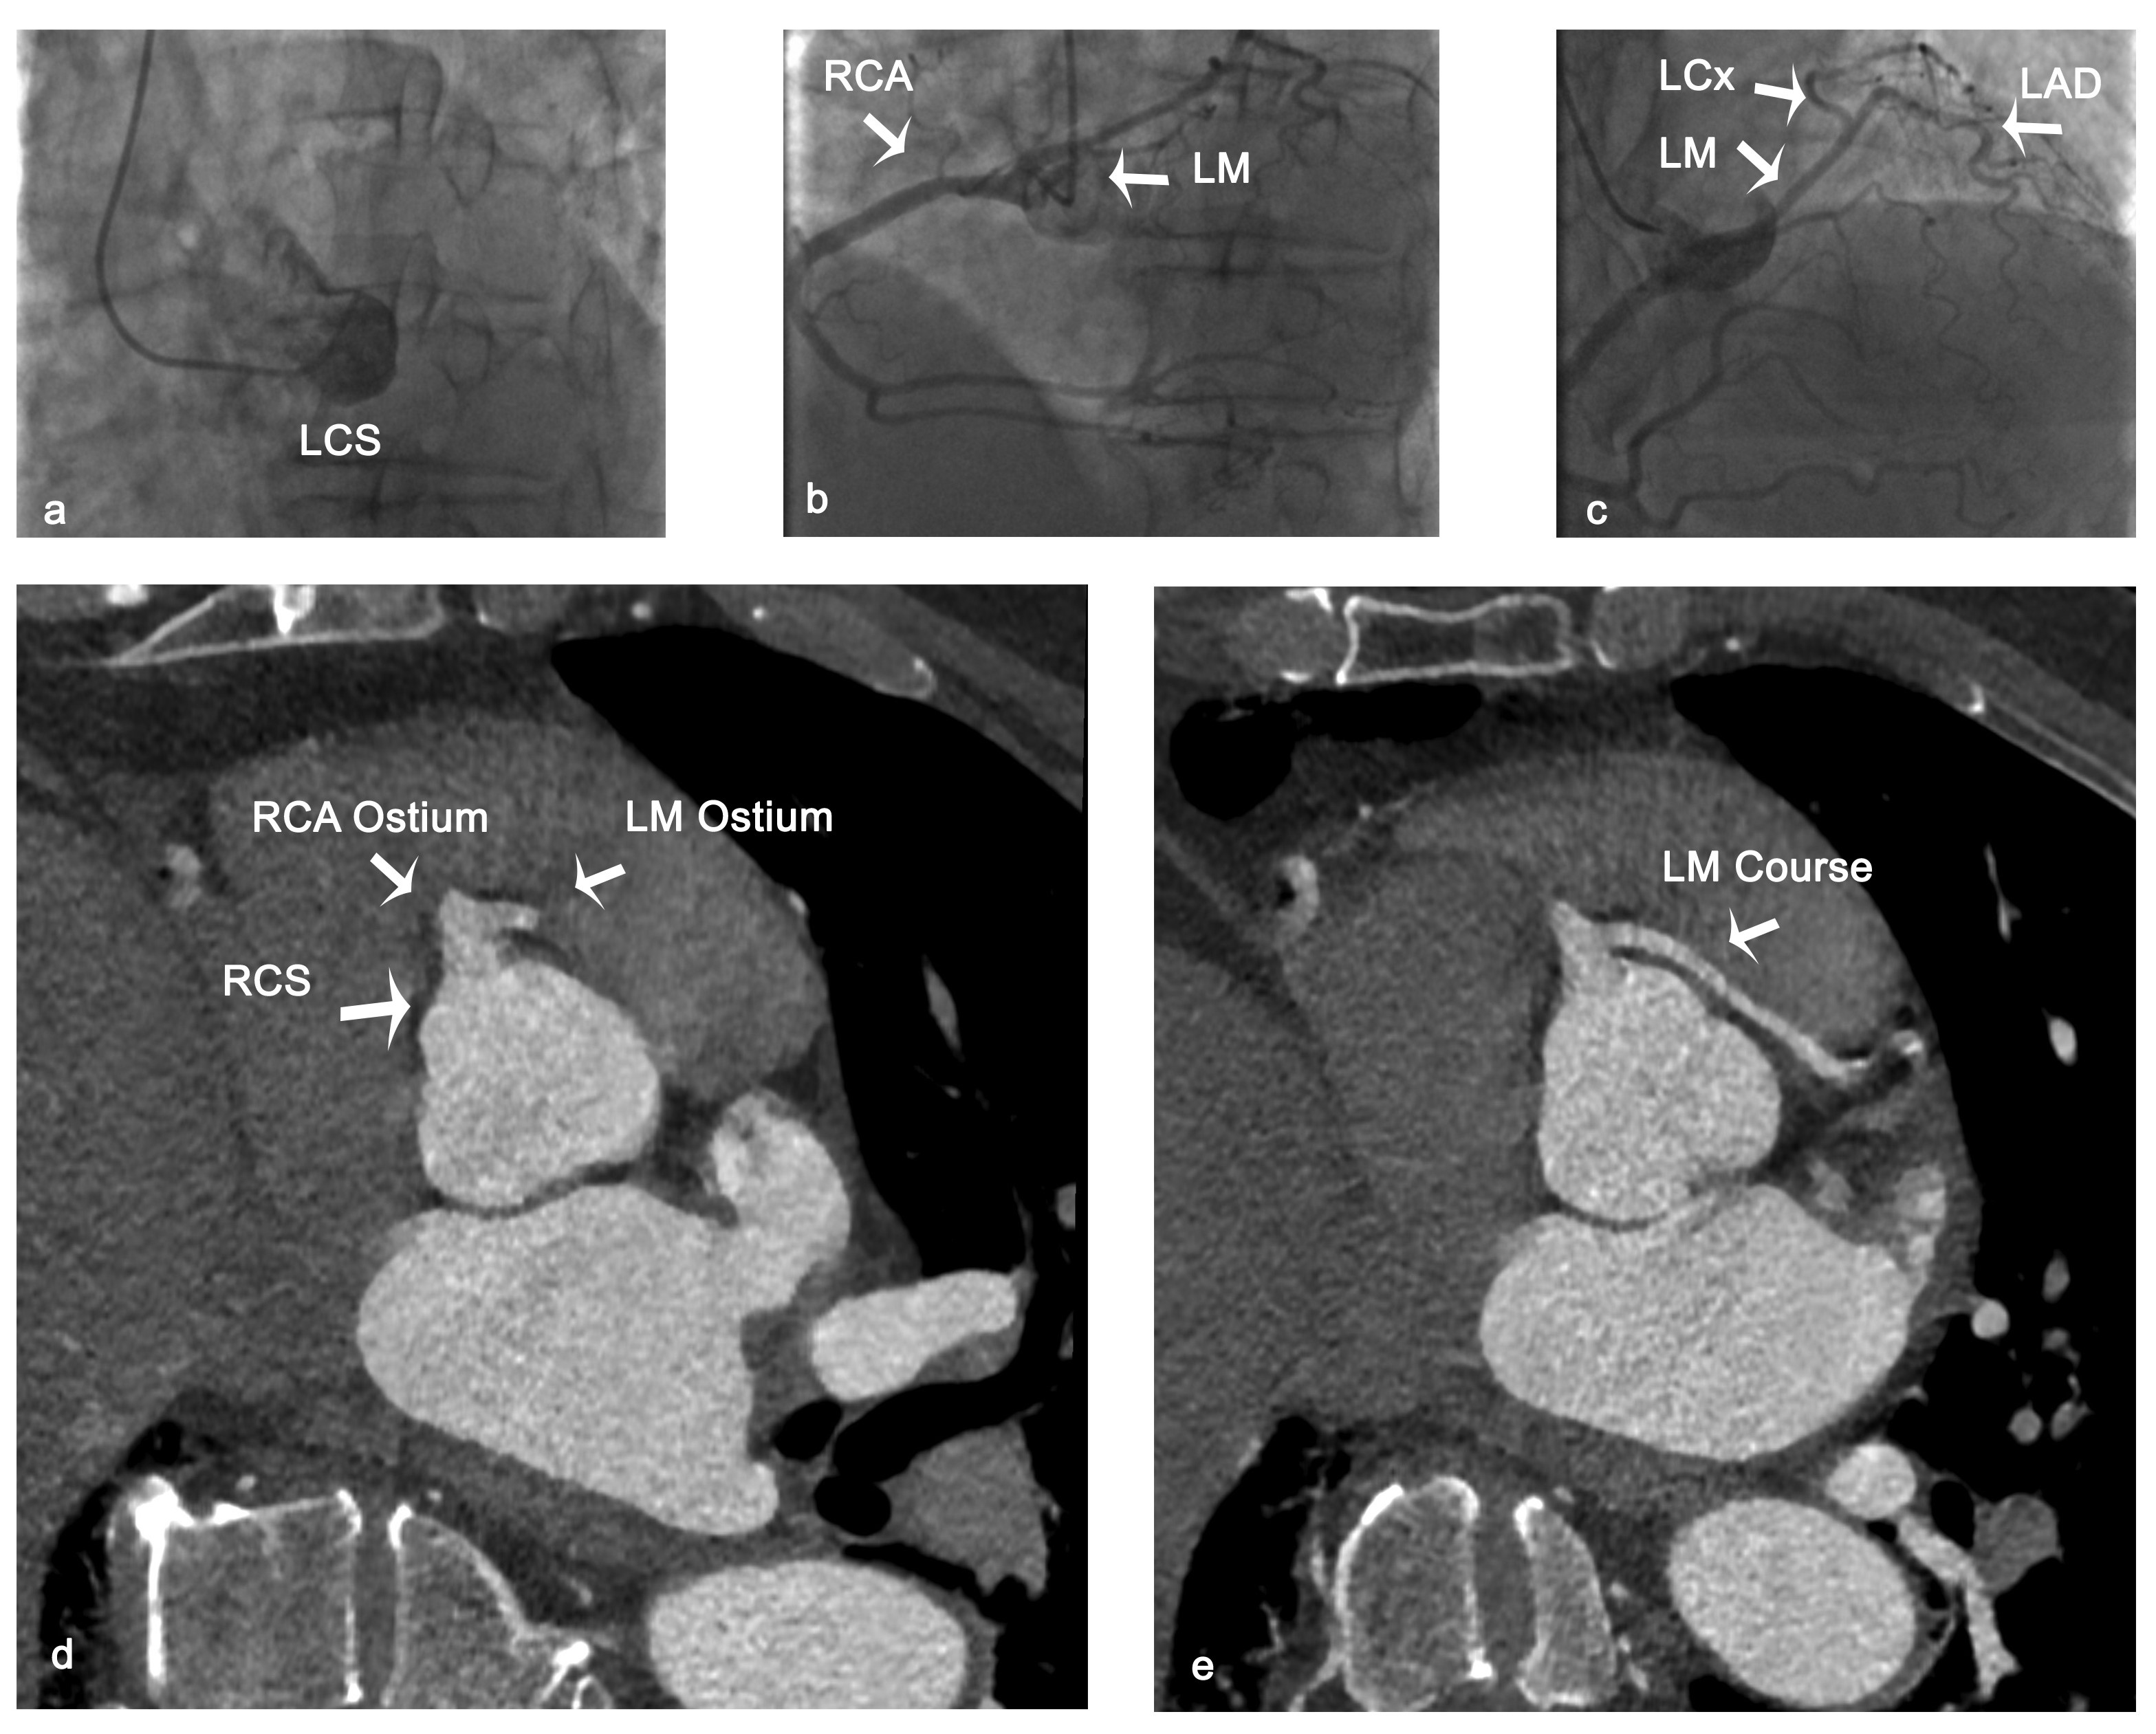

A 55-year-old man was referred to our department for further evaluation of an episode of syncope with significant elevation of troponin (2.800ng/L) after strenuous exercise. We performed coronary angiography, which showed a single coronary artery originating from the right coronary sinus. Significant coronary artery disease was excluded (Figure A-C).

Computed tomography-coronary angiography confirmed the common origin of the left main coronary artery (LM) and the right coronary artery, and revealed an anomalous, long interarterial course of the LM between the aortic root and the pulmonary artery (Figure D and E).